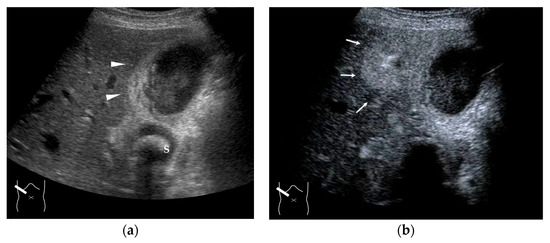

4.1. HHT-Related HV Abnormalities

4.2. Congenital P-V Shunts

4.3. Budd–Chiari Syndrome